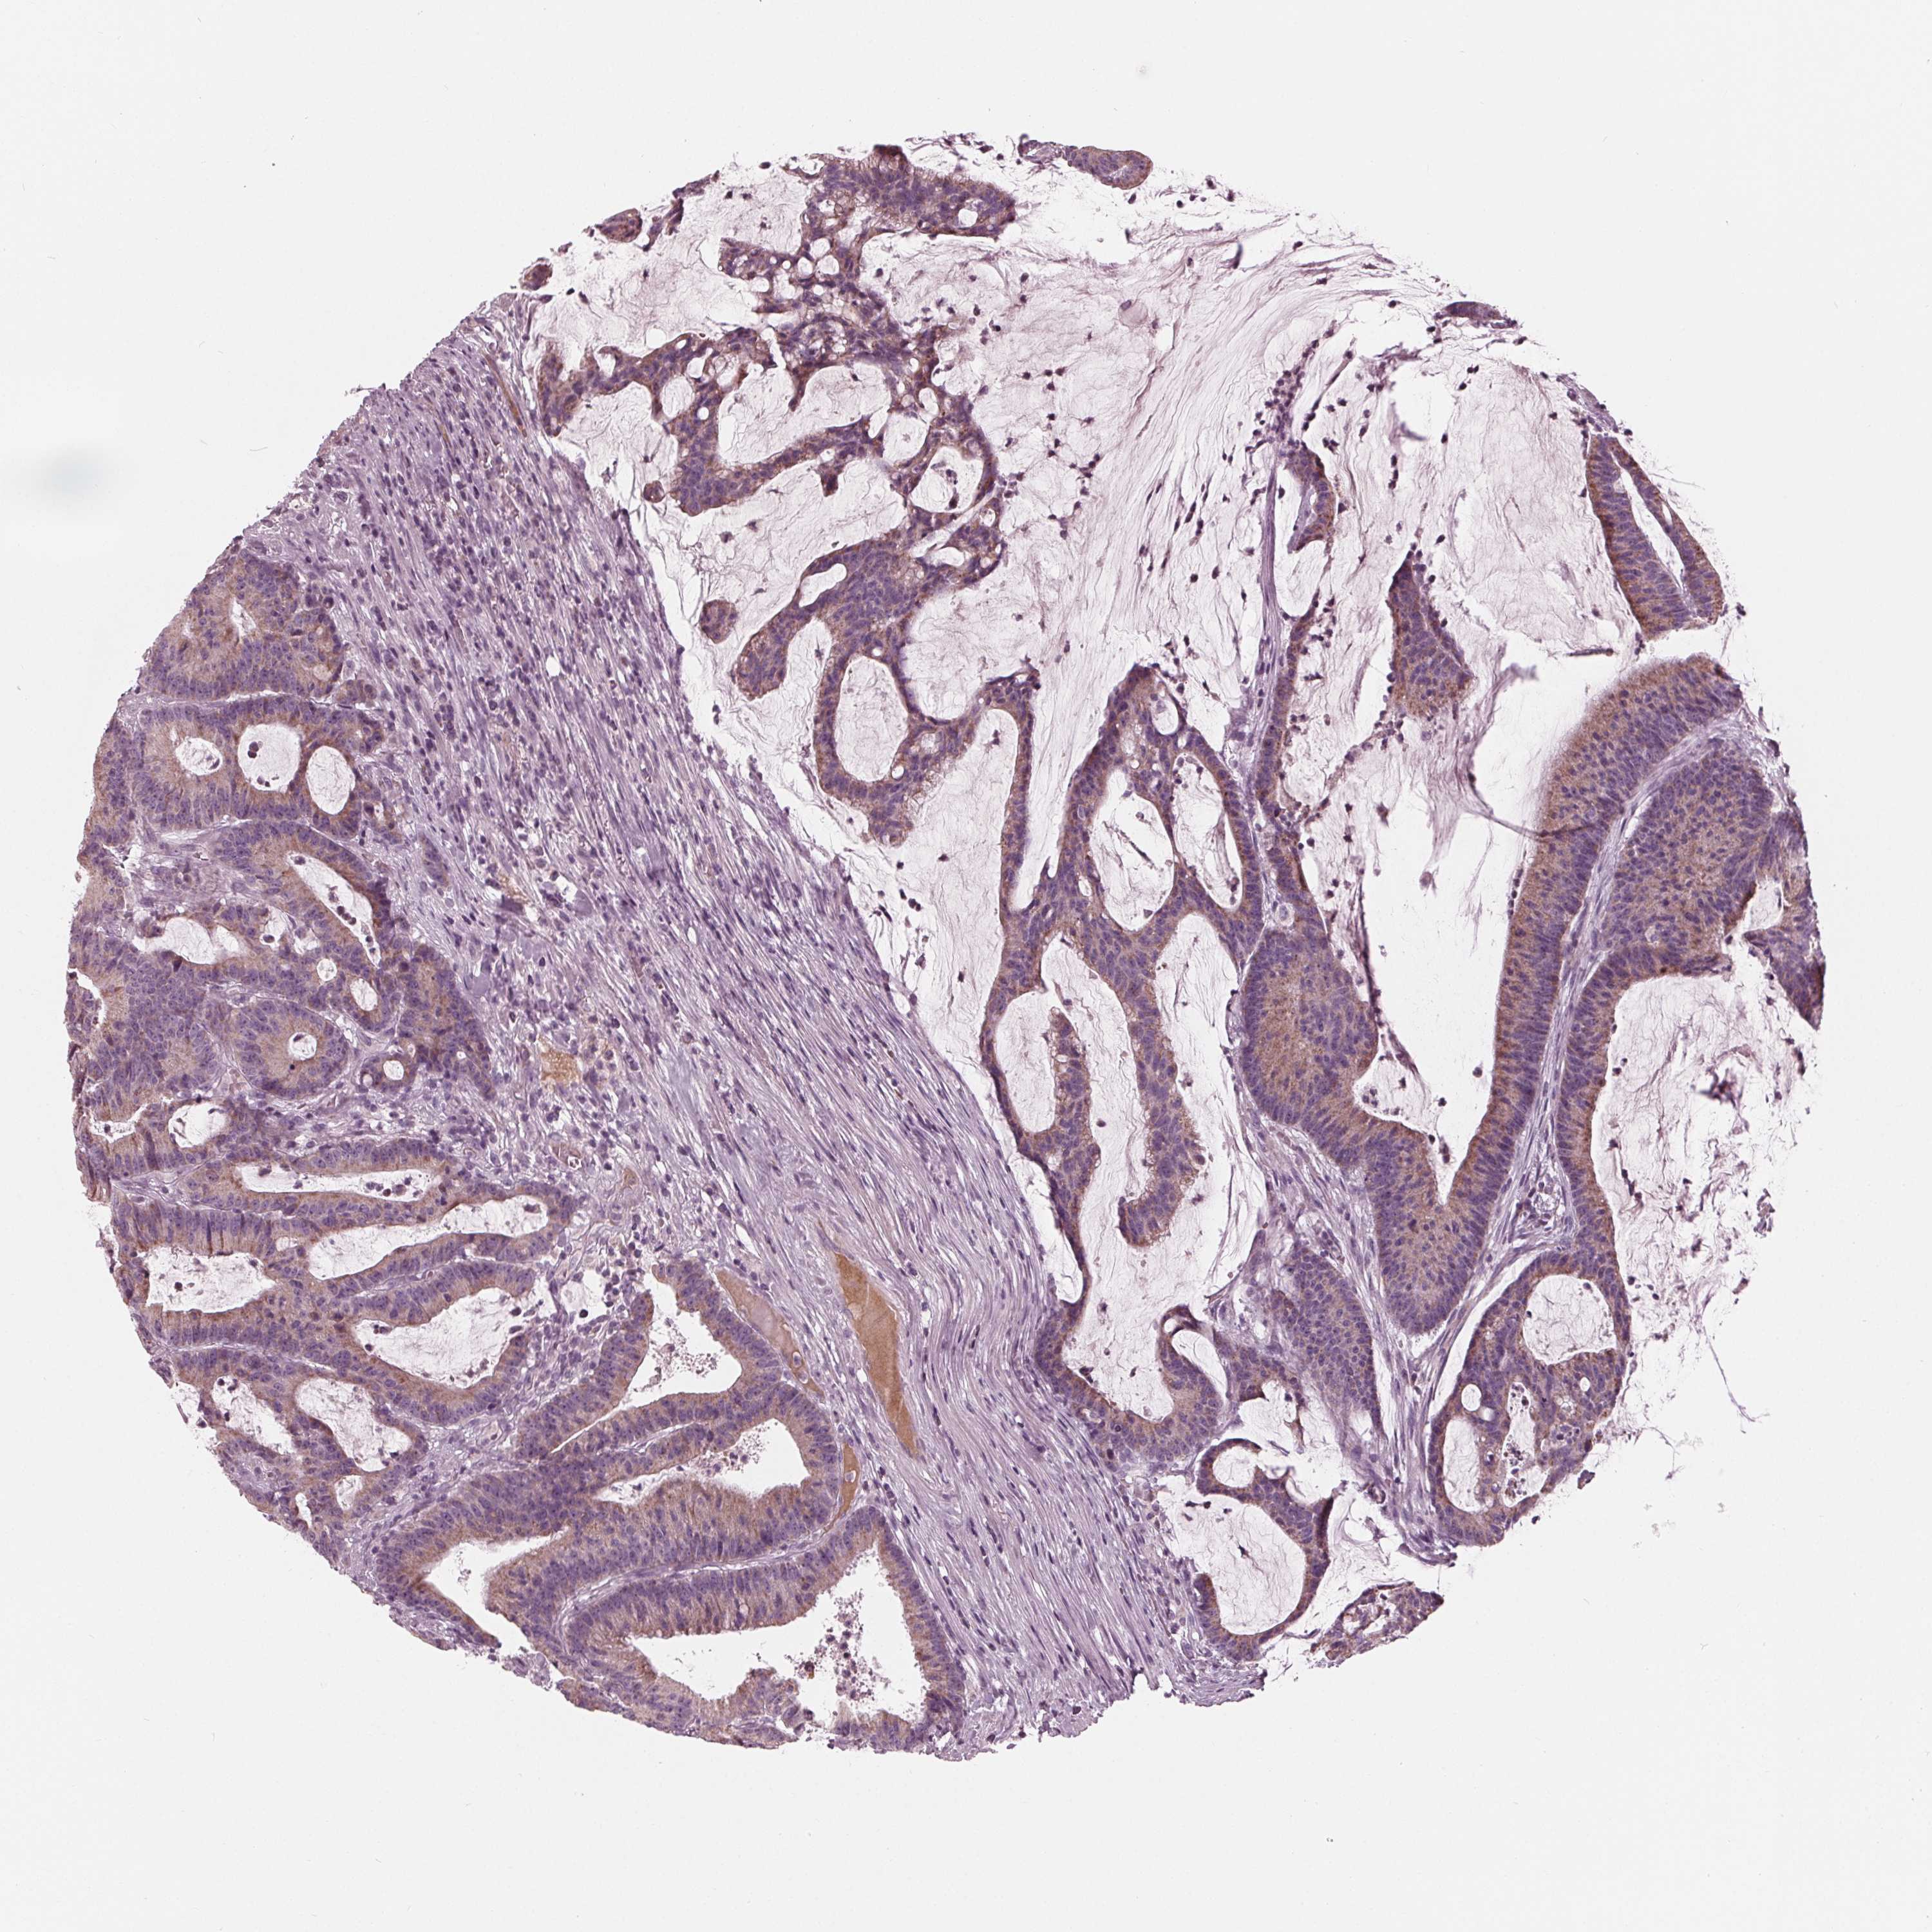

CANCER COLORECTAL CANCER Show tissue menu

Colorectal cancer

Human cancer

Colon adenocarcinoma